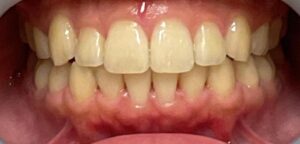

症例1 前歯の歯並びが後戻りによって出てきてしまったしまったケース(中等度)

10年ほど前のワイヤー矯正後に、保定装置をつけていなかったことが原因で前歯が後戻りしています。

- 治療方法 インビザライン上下+形態修正

- 治療期間:1年

- 治療費用 ¥759000(税込)

- 治療のリスク・デメリット 保定装置をしないと後戻りする

Before

After